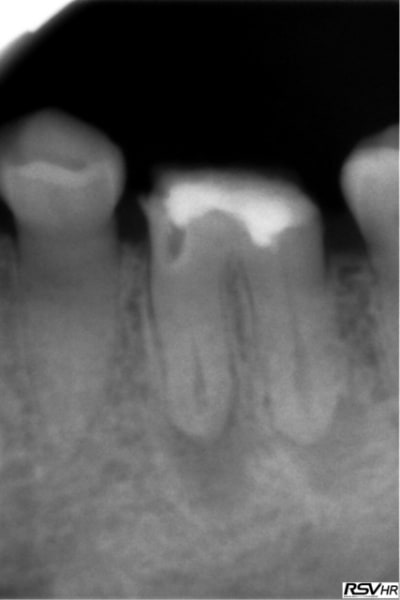

Voici un exemple de couplage microscope opératoire/cbct

RTE 36 en octobre2012 ;3 heures de RTE pour recherche de canaux sous micro inserts ultrasons/il y avait une LIPOE

digue+hypo+système R-endo microméga instruments à mains

vérification au CBCT en 2016

disparition des LIPOE

ici on obtient une guérison apicale